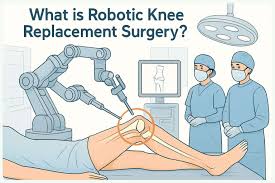

Introduction to Robotic Knee Replacement Robotic knee replacement in Korba …

Introduction to Robotic Knee Replacement Robotic knee replacement in Khairagarh-Chhuikhadan-Gandai …